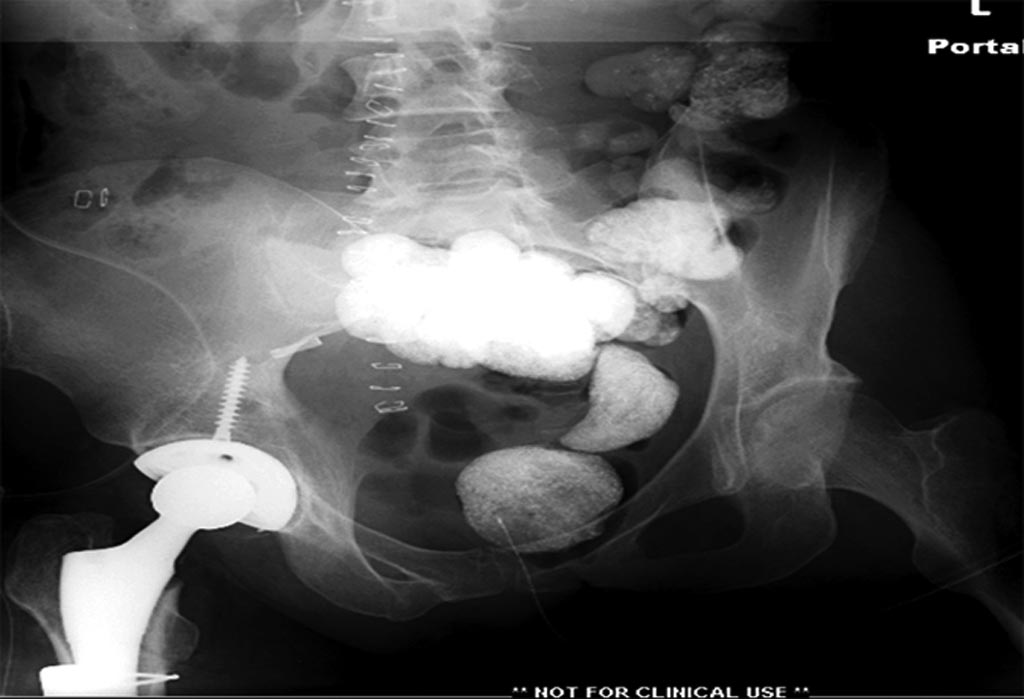

На 25 день с момента травмы операция на Jackson table с боковым обширным

доступом. Удаление стержней с местной обработкой. В тазобедренном

суставе удаление головки, на дне вертлужной впадины полная отслойка

хряща. Вертлужный компонент с одним винтом и короткая ножка -  Fitmore

press fit stem. На второй день однократно доза радиации для профилактики

гетеретопической оссификации.  Послеоперационный период без температуры.

Выписана. Нагрузку разрешили на левой стороне, а полная в 3 мес.  Здесь

снимки при амбулаторном наблюдении​: послеоперационно, 2 мес, 3 мес и 6

мес. Нагрузка полная, отсутствует хромота, и нет жалоб.